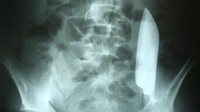

Seorang pria 22 tahun di Nepal pergi ke rumah sakit karena keluhan sakit perut. Ternyata, ada pisau berukuran 5 inci atau sekitar 15 cm menyangkut di dalam perutnya. (Foto: Cureus Journal of Medical Science)